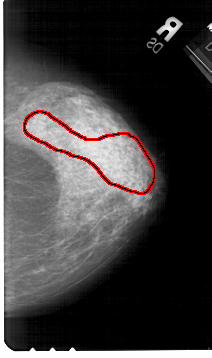

A_1511_1.RIGHT_MLO

RIGHT_CC LINES 5356 PIXELS_PER_LINE 3166 BITS_PER_PIXEL 12 RESOLUTION 43.5 OVERLAY

FILE: A_1511_1.RIGHT_CC.OVERLAY

TOTAL_ABNORMALITIES 1

ABNORMALITY 1

LESION_TYPE CALCIFICATION TYPE AMORPHOUS DISTRIBUTION SEGMENTAL

ASSESSMENT 4

SUBTLETY 3

PATHOLOGY BENIGN

TOTAL_OUTLINES 1

BOUNDARY